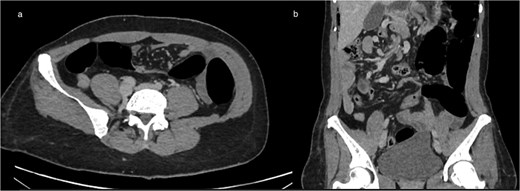

(a) Axial contrast-enhanced CT showing the classic ‘whirlpool sign,’ with clockwise swirling of the superior mesenteric vein and mesenteric fat around the SMA, consistent with midgut volvulus (b) coronal CT reconstruction confirming mesenteric torsion.

Axial (a) and coronal (b) contrast-enhanced CT images demonstrating intestinal malrotation, characterized by right-sided small bowel loops and left-sided colonic segments, with an abnormal relationship between the SMA and vein.